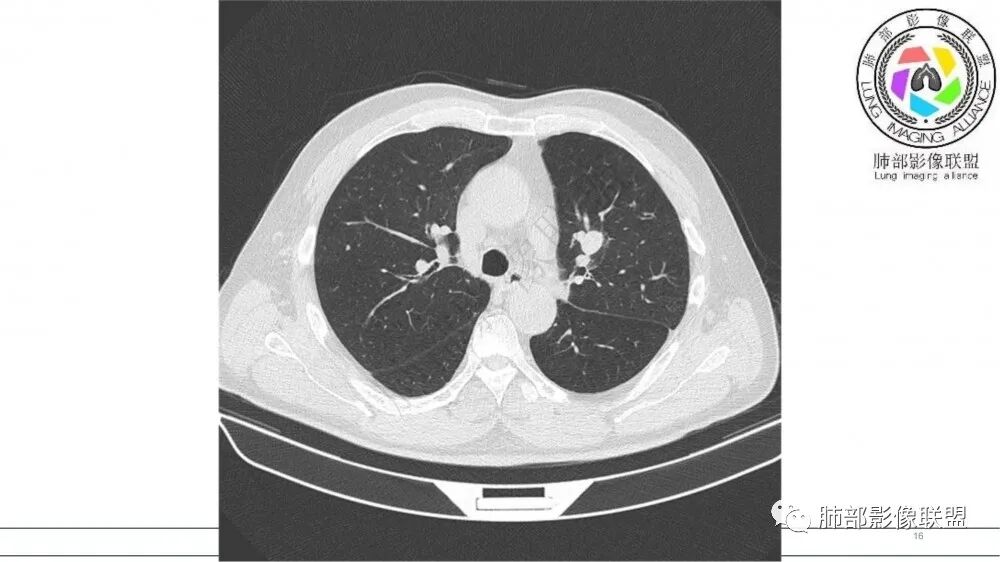

猜个鳞,沿支气管塑型生长,周围小花小草,肺门及纵隔淋巴结增大,吸烟老年男。鉴别TB

左肺上叶前段支气管内铸形生长软组织影,增强后均匀强化,远侧见斑片状磨玻璃影。考虑恶性病变,粘表?粘液腺?

左肺上叶前段支气管杵状指样扩张,内见实性组织阻塞性,并强化明显,边缘饱满,周边多发小斑点影,小花小草征,老年男性,长期吸烟史,方向恶性,首选支气管内浸润鳞Ca可能性大。

男,70岁,吸烟史,咳嗽,胸闷憋气一个月,左肺上叶不规则形软组织密度影,病灶沿支气管走形,周围见粟粒及棉絮样稍高密度影,增强扫描病灶内见少许坏死,考虑鳞癌可能,鉴别结核。

老年男性,肺气肿,吸烟史,左肺上支气管腔内铸型高密度影,呈指套状,远端多发树芽,增强不均匀强化,考虑鳞癌,鉴别小细胞癌

B3指套征,常规不是鳞癌就是ABPA,有强化丶血管造影征,倾向于鳞癌

老年男性,长期吸烟史。左上肺前段沿支气管走形的指套样病变,增强可见病灶强化(排除结核、ABPA(也无气喘症状)),远端多发点状高密度影。考虑恶性肿瘤,鳞癌可能性大。

指套征明确吧

有强化吧,淋巴结大

指套征,扩张支气管内软组织强化,远侧肺野阻塞性炎,纵隔、左肺门肿大淋巴结;老年男性,吸烟,考虑鳞癌,鉴别小

2021年8月6日晨读病例结果:小细胞肺癌

指套征:是影像征象,胸部平片表现为手指状密度增高影,以肺门为中心呈放射状分布,CT显示扩张支气管内低密度黏液栓形成或实性病变,呈管状、树枝状或卵圆形密度增高影;支气管扩张伴近端梗阻时,扩张支气管内部黏液分泌物不能排出而形成。可以伴随远端空气潴留征、阻塞性炎症。

研究报道,中心型 SCLC 经 CT 扫描后通常支气管表现为鼠尾样狭窄,肺门或纵隔肿块明显,由于肿块沿管壁生长表现为顺延支气管形态的不规则形状。病灶相对特征性影像学表现比如鸭蹼状、腊肠状、葫芦状及葡萄状改变,可以出现血管包埋,很少有空洞、空泡,较少引发肺不张,阻塞性炎症成都较轻。与一般肺癌比较,恶性程度高,侵袭力强、病灶很小就容易远处转移!Herzberg 等[19]研究指出,20%以上 SCLC 倍增时间短,预后不良。